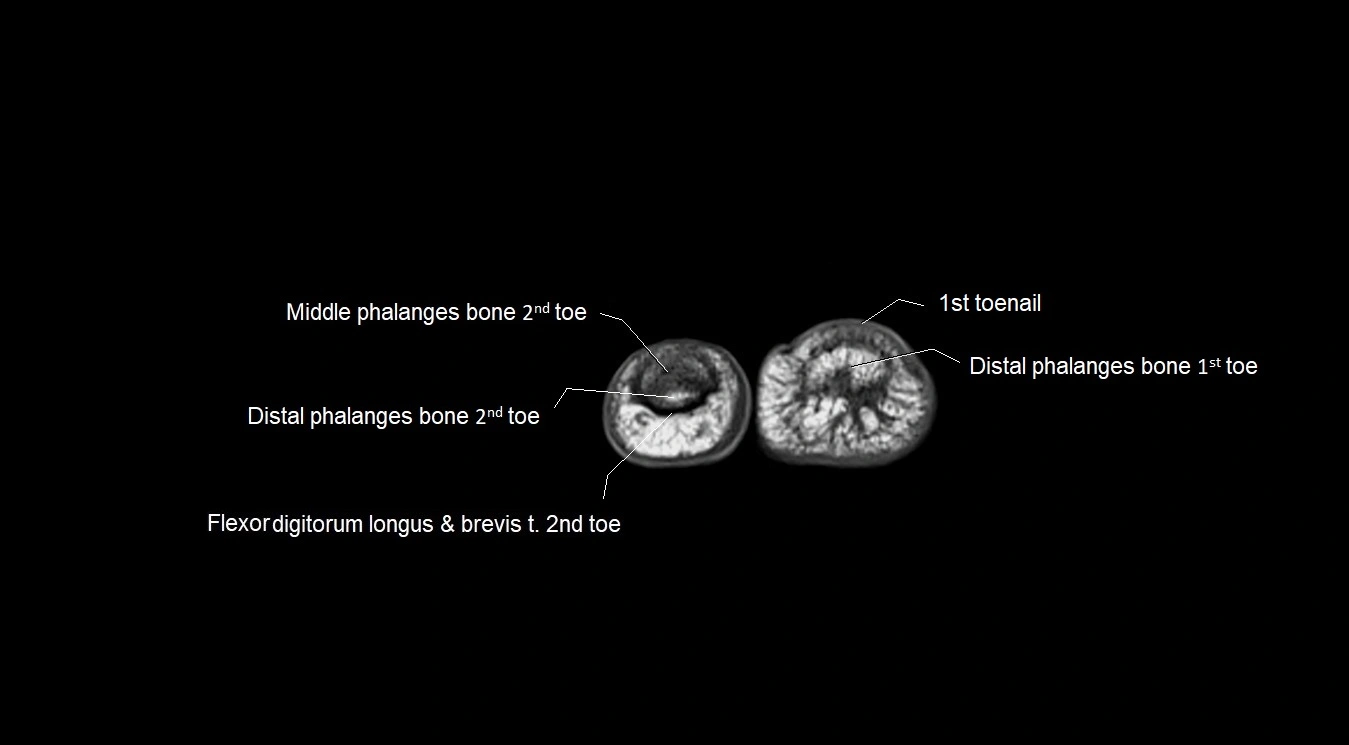

MRI image